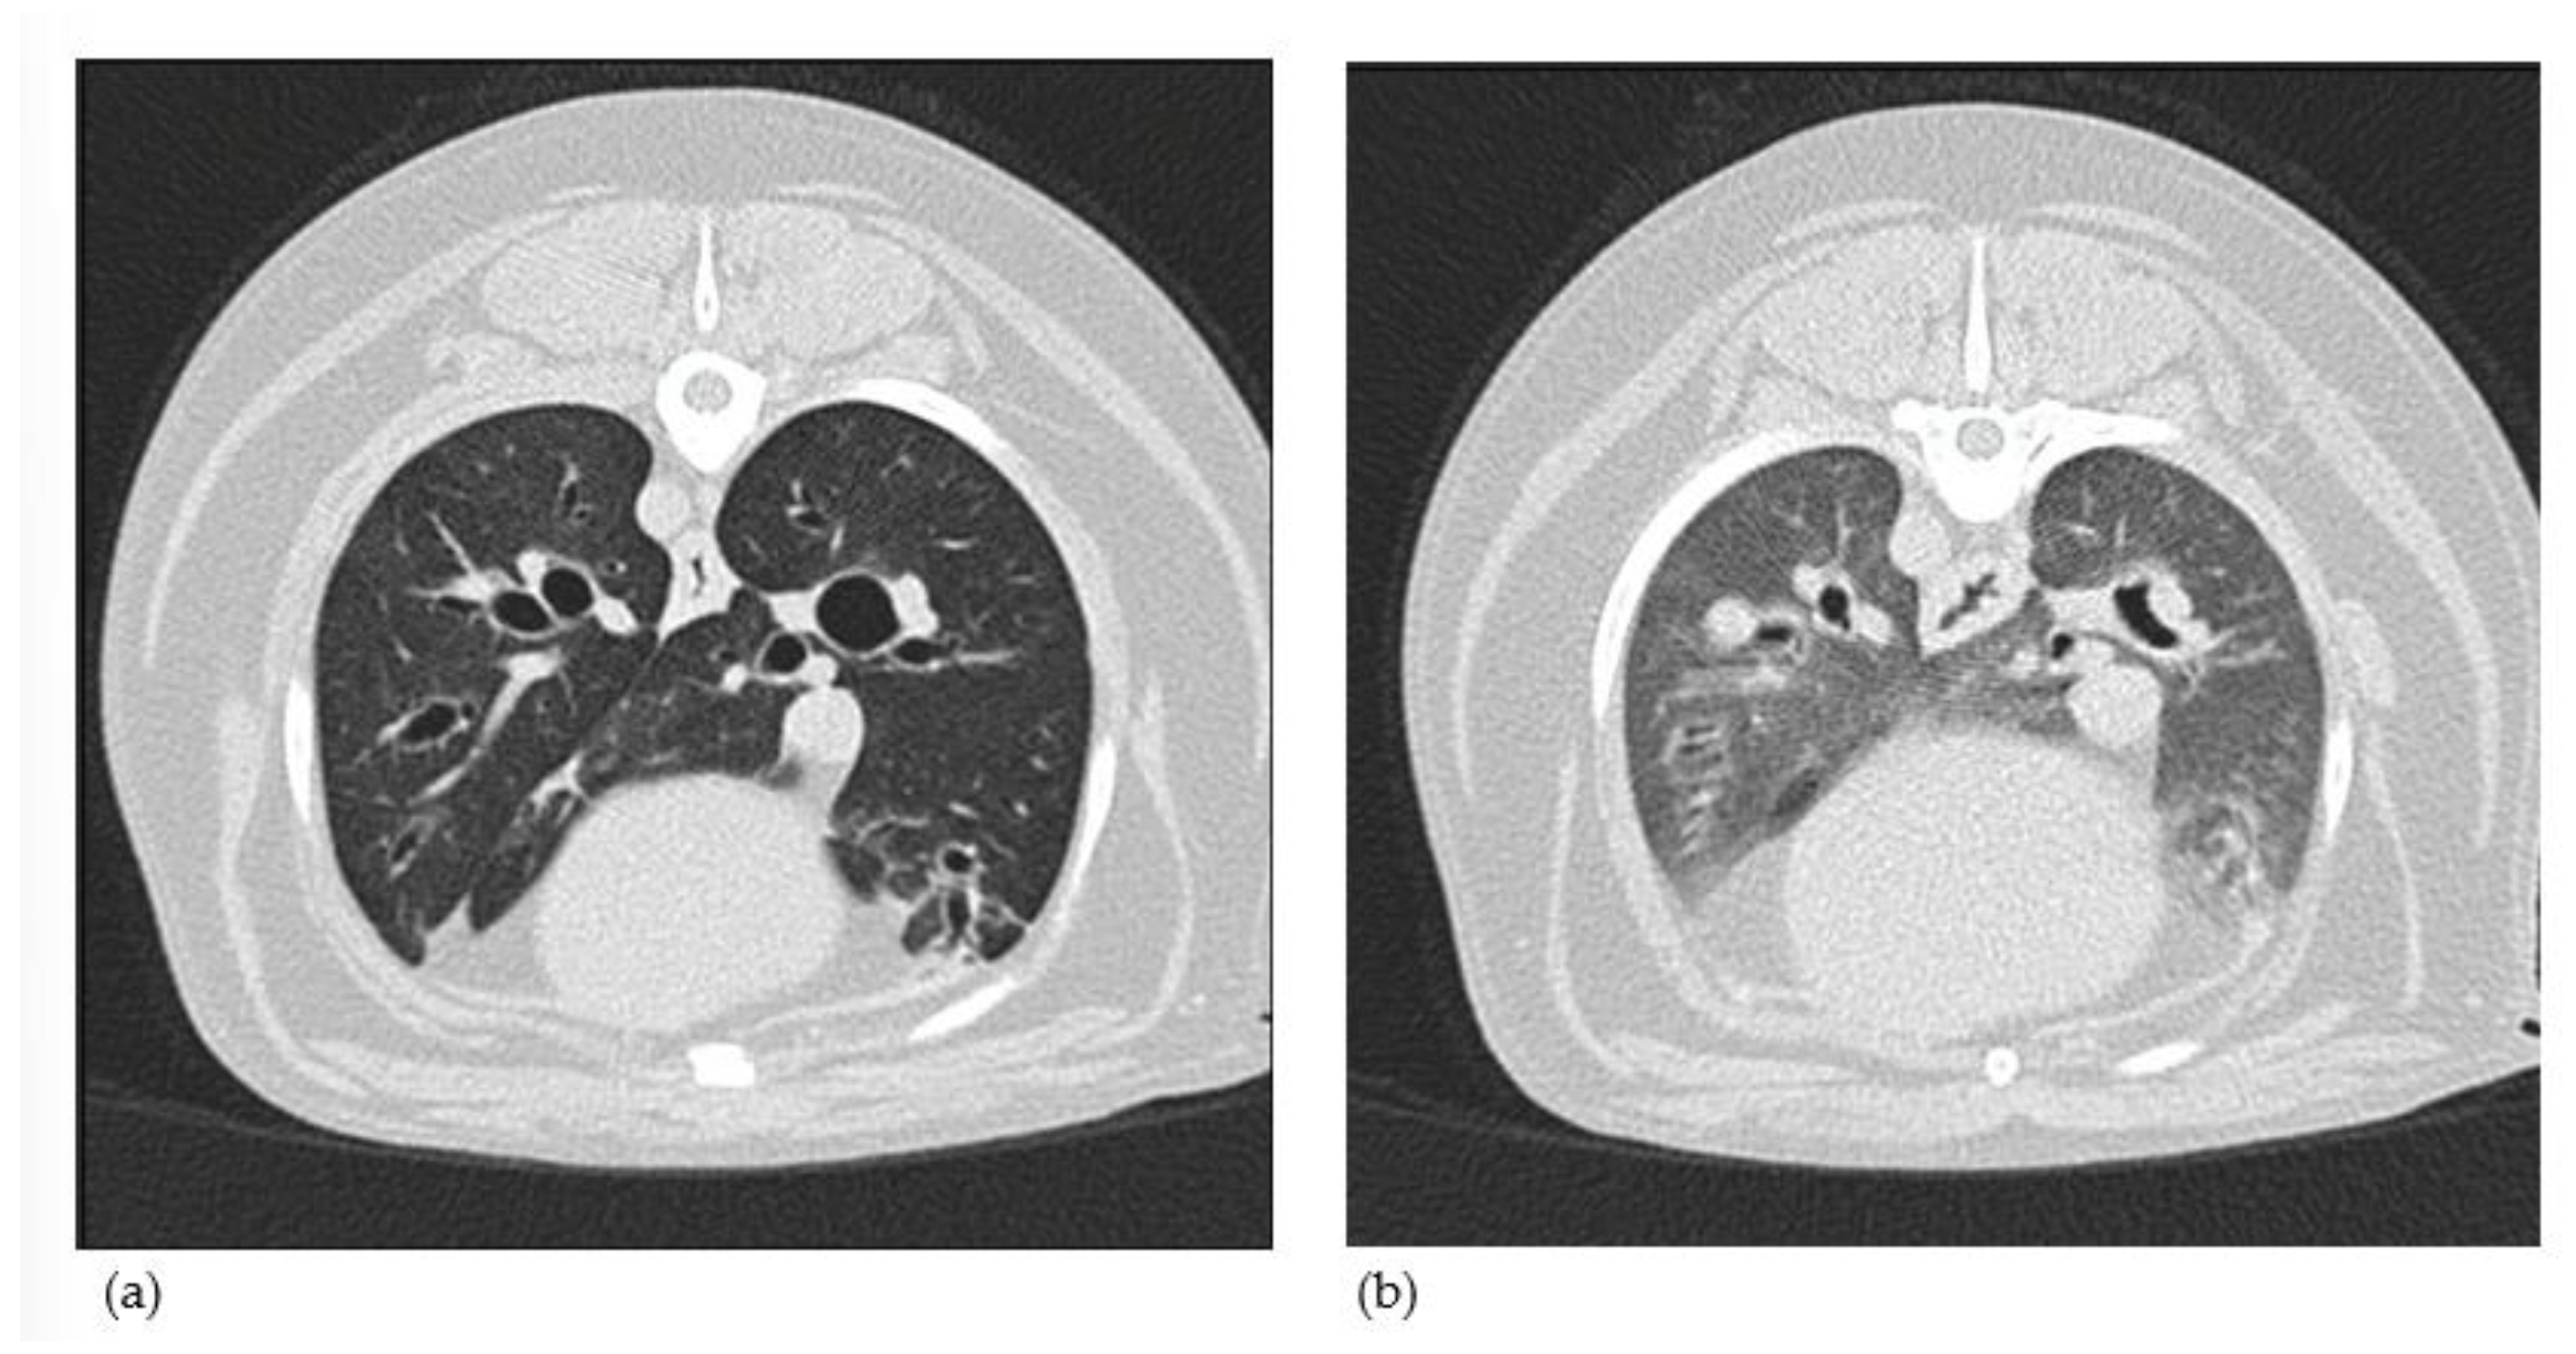

3.1.8. Computed Tomography Findings

3.2.2. Thoracic CT Versus Endoscopy